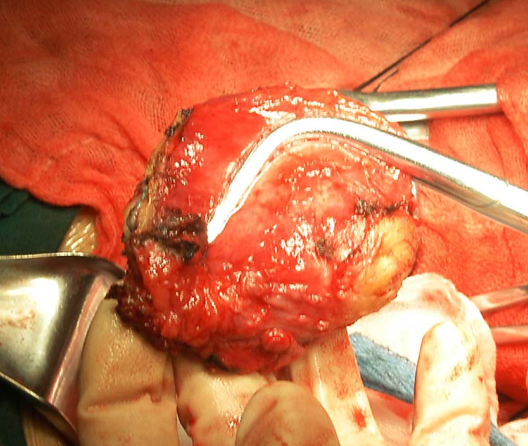

Ⅲ型即广泛子宫切除术标本 盆腔淋巴结切除术标本